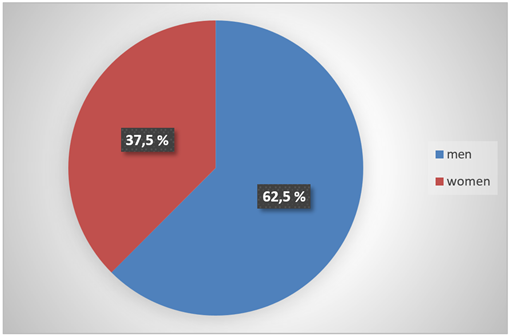

2/ Distribution of patients by sex: There was a clear male predominance, with a sex ratio (M/F) of 1.66, i.e., 62.5% men and 37.5% women (Figure 2).

Figure 2: Distribution of patients by gender.

Male predominance dominates in our study, with a sex ratio (M/F) of 1.6, i.e. 20 men vs. 12 women. This male predominance was present in several series: 62.5% of men in Benchekroun's series [6], 63% of men in Bennani's series [7], 56.1% of men in EL KHADER's series [8] and finally 73% of men in SOW's series [9].